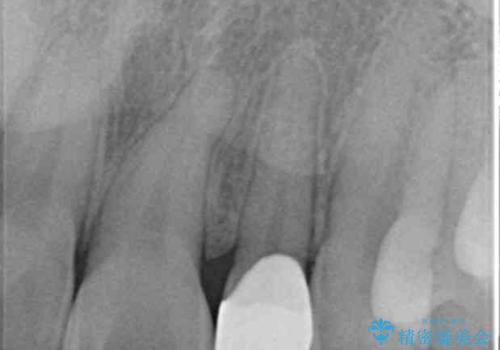

- 左上の前歯が生まれつき小さく、前に飛び出していました。

矯正治療で引っ込めてから、形を左右対称に整えるセラミック治療を行いました。